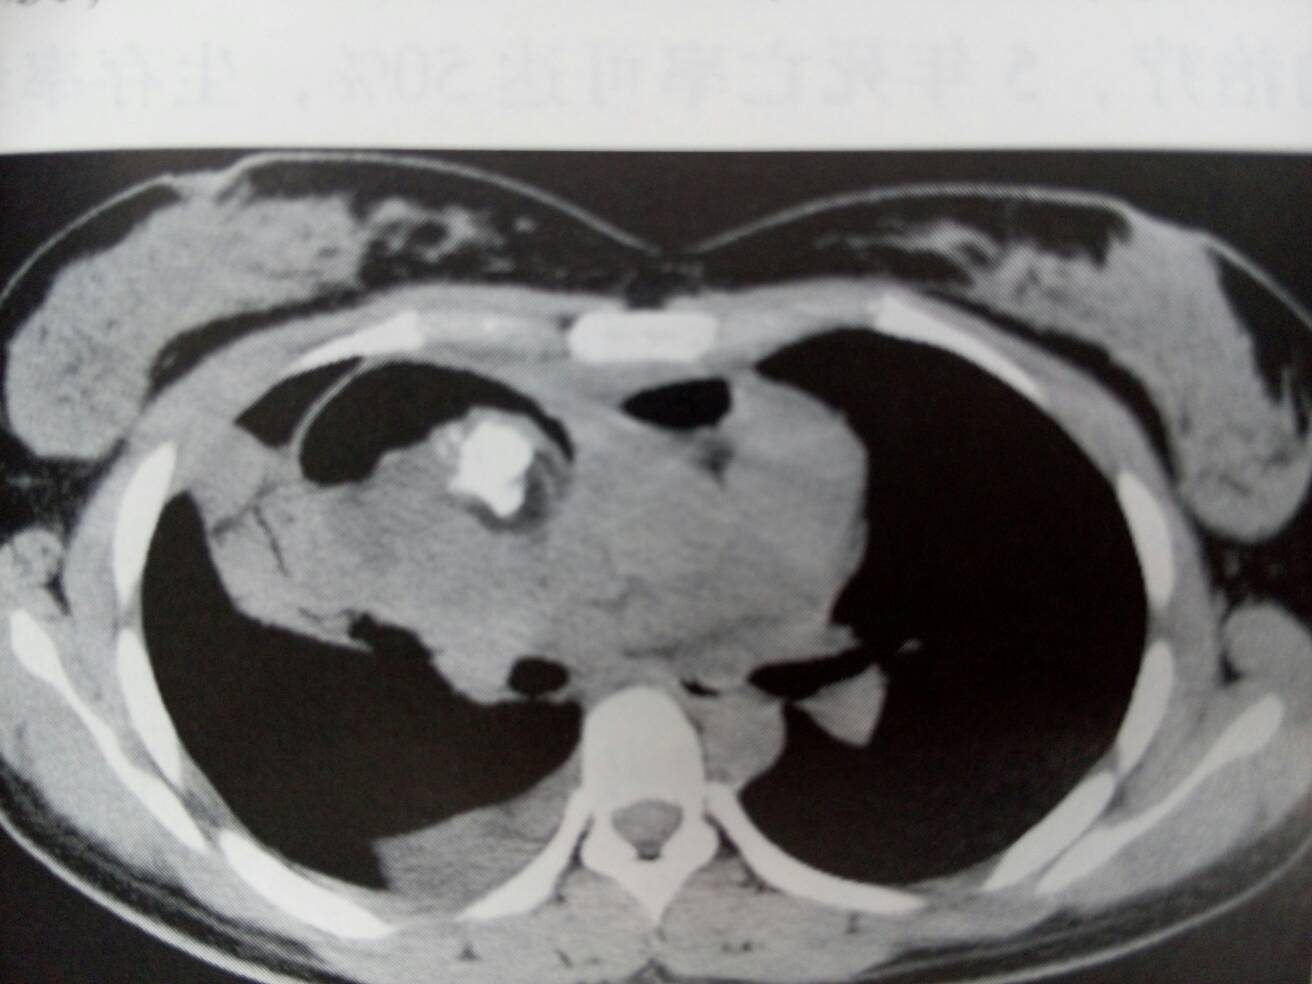

患者,女性,发现右下腹包块10个月。患者于10个月前体检时发现右下腹包块,当时未予注意,现为求进一步治疗收入我科。16/12我院门诊阴道彩超示:子宫右附件区囊实性占位,右卵巢畸胎瘤可能性大。(畸胎瘤的成分复杂,可以有脂肪、钙化等,所以CT有脂肪密度,密度不均,如果有钙化是成熟畸胎瘤。成熟畸胎瘤绝大部分为囊性,又名囊性畸胎瘤,占畸胎瘤的97%,可发生于任何年龄,有80%~90%的患者为生育期妇女。畸胎瘤病理类型各异,有壁立性结节征,面团征,脂液分层征,瀑布征,星花征,多囊征,杂乱结构征,线条征等等)该患者彩超图如下,可以看到子宫右上方有一大小约54*48mm的低回声囊实性包块,囊内有一高回声水平界线,上层为液性无回声区(黑色部分),亦可见液内悬浮少量光点,下层为脂类物(灰色部分),呈分布均匀的密集细小光点,这畸胎瘤特征之一的脂液分层。因为患者已经打算做手术的了,所以没有做盆腔CT,下面这三张盆腔CT是我叫白开水给我找的,我挺不厚道的借用了他的图,有怪莫怪,有怪莫怪哈。。。。。。患者今天做了手术,切除物已经送病检了,但是病检估计要一周才可以回来,到时追踪下病检再补充好了。。。